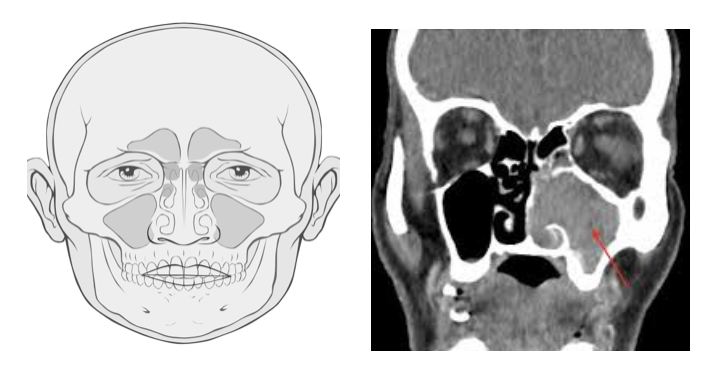

80% of tumors in this region originate from the maxillary sinus located behind both cheek skins. Tumors (Squamous Epithelial Cell Cancer) resulting from the mucosa covering the sinus cavities occur in 80%.

The first choice as radiological imaging is computed tomography. This method evaluates the condition of the bone structure and whether the bone is invaded with the tumor. With MRI imaging, soft tissues are evaluated and inflammatory tissue-tumor separation is made more accurately.